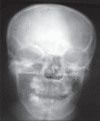

Congenital infiltrating lipomatosis of the face is a rare condition characterized by diffuse fatty infiltration of the facial soft tissues. There may be muscle involvement along with associated bony hyperplasia. It is a type of lipomatous tumor that is congenital in origin; it is rare and seen usually in childhood. We recently saw an 11-year-old girl with this condition. She presented with a swelling of the right side of the face that had been present since birth; there were typical findings on plain radiographs, CT, and MRI. The patient underwent cosmetic surgery. Histopathological examination showed mature adipocytes without any capsule.